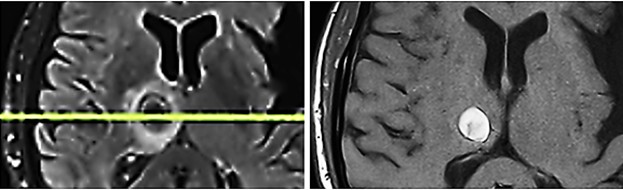

Fig. 5

Fig. 5: Metastasis in the right thalamus before transcranial TMI treatment with pronounced perifocal edema (left) and five months after TMI treatment; notably the brain tissue is not impaired by the transcranial TMI treatment (right).

After transcranial TMI treatment as described, the patient was becoming increasingly alert and showed improvement in all neurological investigations. With the support of the physiotherapist, he could now walk short distances and climb one flight of stairs, use the toilet independently, his spatial awareness was steadily improving, he could eat independently, and had complete recollection of all events up to the onset of somnolence. He had no memory of the eight weeks of somnolent state. A follow-up MRI of the skull shows the previously identified hemorrhagic area surrounded by a glial capsule and a perifocal edema, but no further progression of the metastasis. The TMI reated thalamic metastasis had shrunk considerably though it is unsure if there remained still vital tumorous tissue (Fig. 5). It must be underlined that the surrounding brain tissue was not impaired or damaged by TMI treatment, so that the patient clinically improved, unexpectedly gained again full neurological control, could leave the hospital and return home.